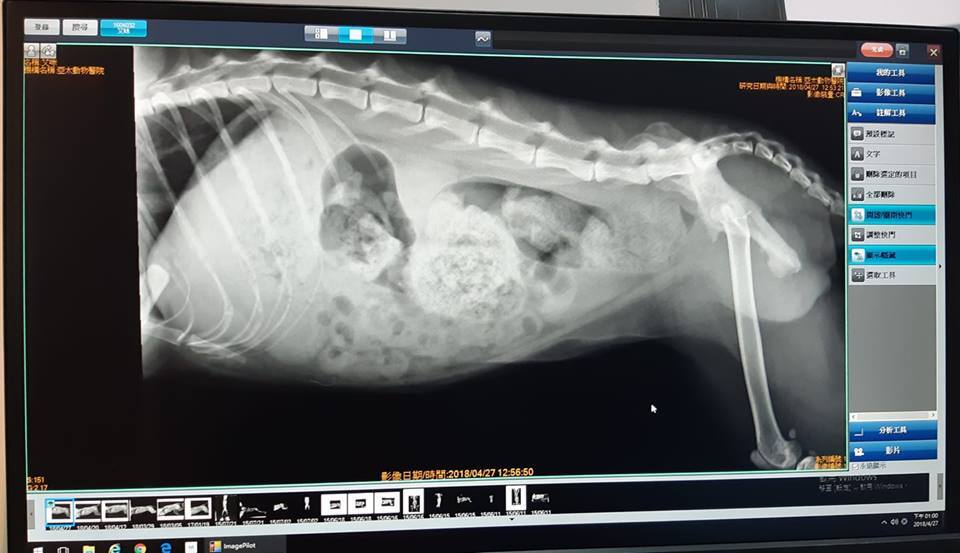

4/27 艾咪 亞太回診 今日看診醫師:許醫師

體重:3.10 (4/20-2.91kg)

體溫:38.5

今日回診情形:

醫師看過照護員照片記錄,認為艾咪這幾天的便便偏硬且數量不夠多,且因艾咪一直有積便問題,因此安排X光檢查,發現艾咪在肛門近出口處有不少較硬的積便,當場試圖為牠挖出便便,但艾咪今日較緊張,無法順利挖出,因此安排明日為牠鎮定後再行挖出便便。

醫囑:

1. 明日(4/28)下午4點回診鎮定挖便便(有可能會改為4:30,若有更改,醫院4/27晚會連絡安安黃),術前需禁食12小時、禁水3小時。

2. 禁食期間,用藥項目照舊。

(A)杜化液 - 早、晚各【3.5cc】

(B)腸胃蠕動劑--早晚各半顆

(C)化毛膏 - 早晚各3cc

(D)食慾促進劑用藥,早晚各一顆

食慾促進劑於4/27早上已餵完最後一顆,醫師說今日暫不再開,待明日挖除便便後再看情況是否需要。

二、

照護員如有看到艾咪正在痾便便,請試著錄下影片,醫師想看牠痾便便的動作。